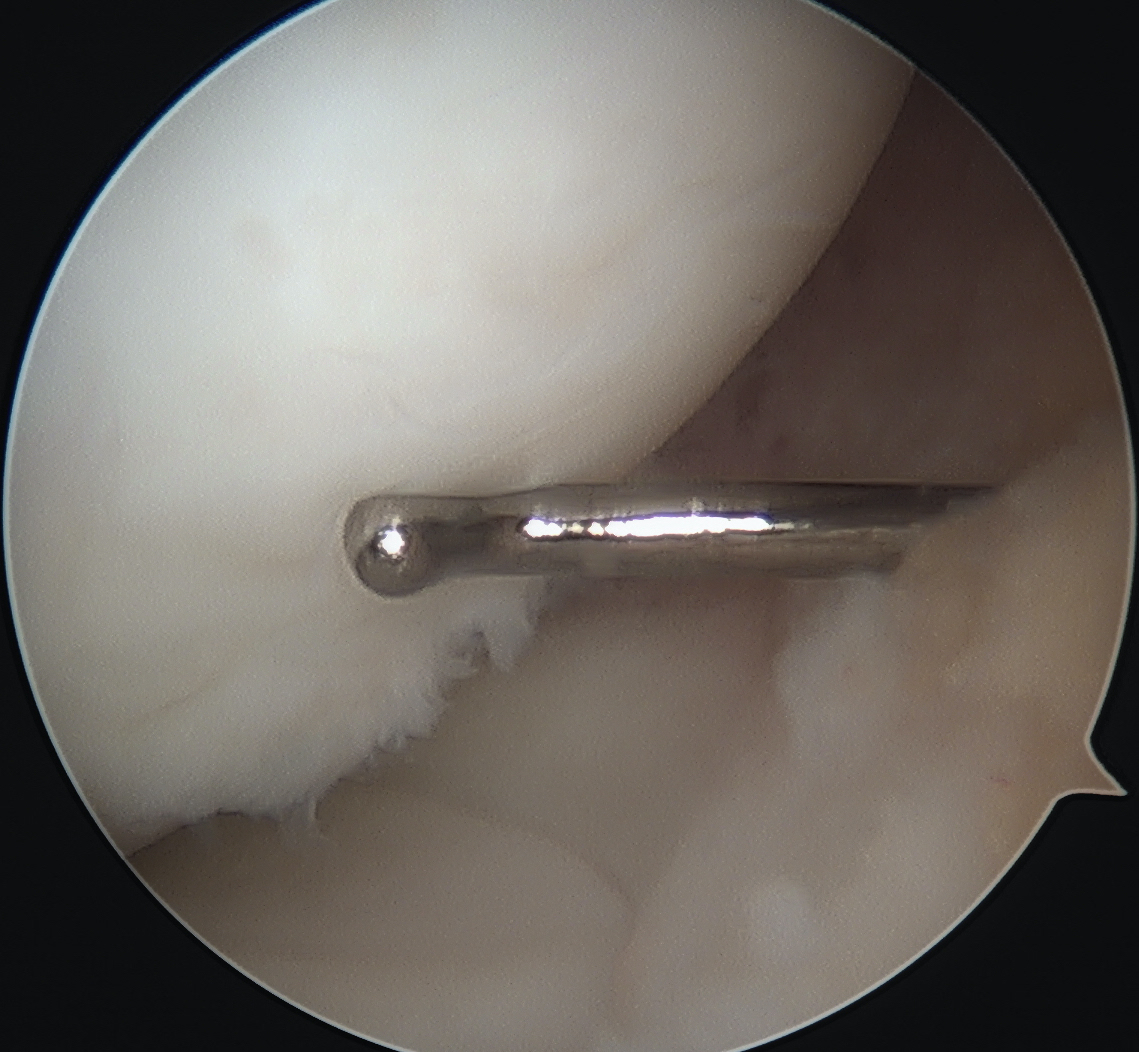

- ensure K wires centered in fragment

- typically 2 - 3 screws maximum (3.5 mm)

- 22 - 26 mm long, want to stop short of growth plate

- ensure screw heads are buried under cartilage, but not too deep so they still engage fragment